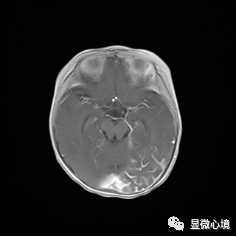

图2 SWS患儿MRI图像,T1增强显示左侧枕顶部软脑膜明显增厚强化

具体来讲,SWS是以一侧三叉神经分布区(V1/V2)不规则红斑、对侧偏瘫、偏身萎缩、同侧颅内钙化、青光眼、癫痫、智能减退为特征的先天性肌病,多为散发病例,少数有家族聚集性,发病率约20/10万。目前认为其可能的发病机制为胚胎发育5-8周时原始血管异常所致,可能涉及血管结构和功能的调控异常、神经支配异常、细胞外基质和血管活性因子的表达异常。依据其临床表现及病变受累范围,将其分为三型,即I型:经典型,有面部红斑、颅内软脑膜血管病变,可伴有眼部病变如青光眼;II型:不全型,有面部红斑、青光眼,无颅内血管病变;III型:非经典型,有颅内软脑膜血管病变,多无青光眼,无面部红斑。临床上症状性(继发性)癫痫,可表现为间断抽搐,发作时双眼向下凝视,下肢持续抖动,不伴口唇发绀、意识丧失、大小便失禁等不适,通常持续几分钟后自行缓解,发作后精神状态好。脑部核磁共振显像(MRI)可表现为病变区脑沟增宽、加深,表面血管增粗迂曲,软脑膜明显增厚强化。